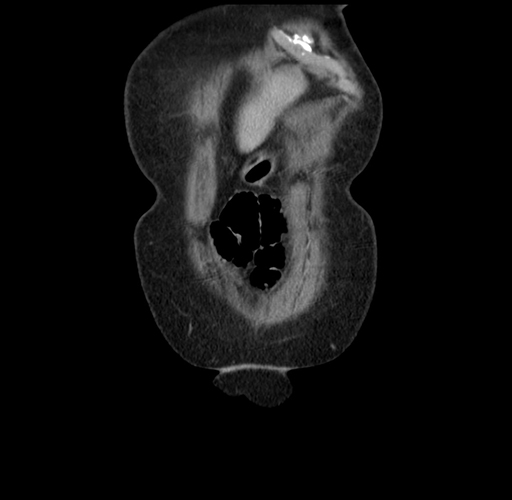

Pre-Chemo: Axial Venous